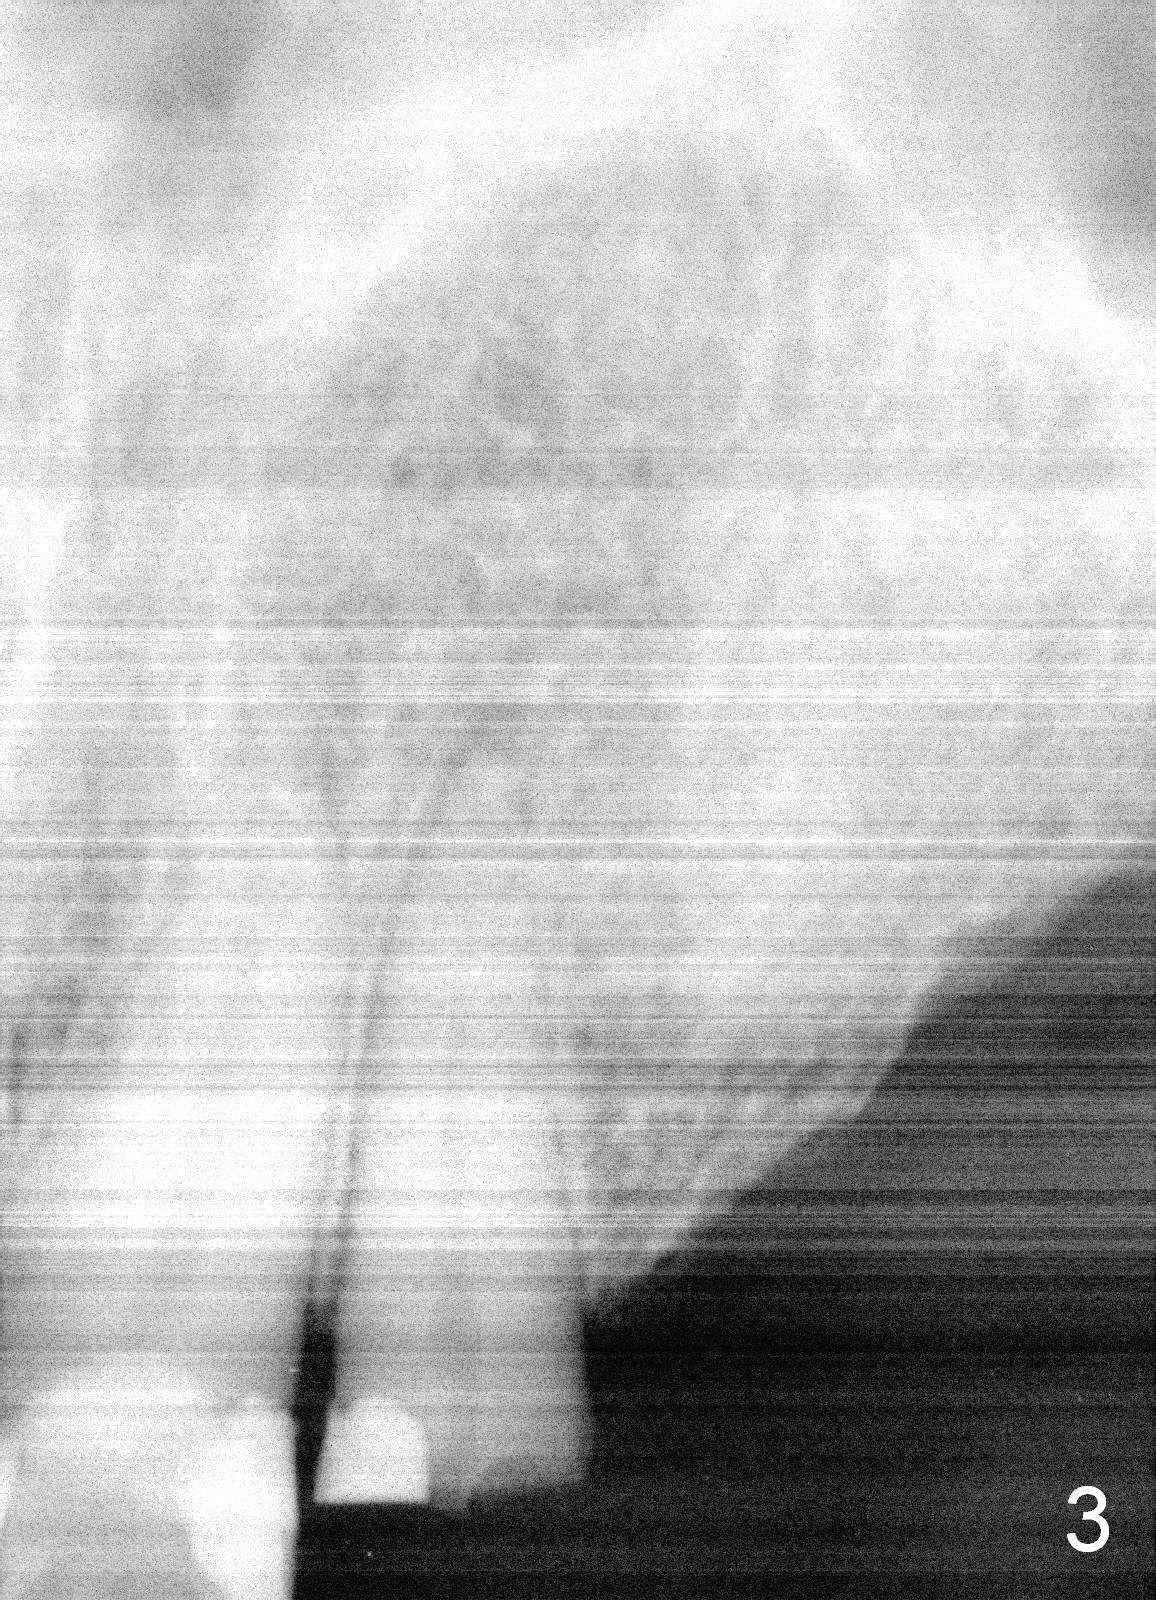

A 70-year-old man (TF) requests implant restoration for the upper left quadrant first (Fig.1), exactly #10 and 11 first (Fig.2-4). There is periapical radiolucency associated with the residual root at #10 (Fig.2 *). Local antibiotic will be Metronidazole. The root of #10 is long and large. The bone at #11 looks loose. Long implants will be placed (Fig.4). Osteotomy preparation should be less.